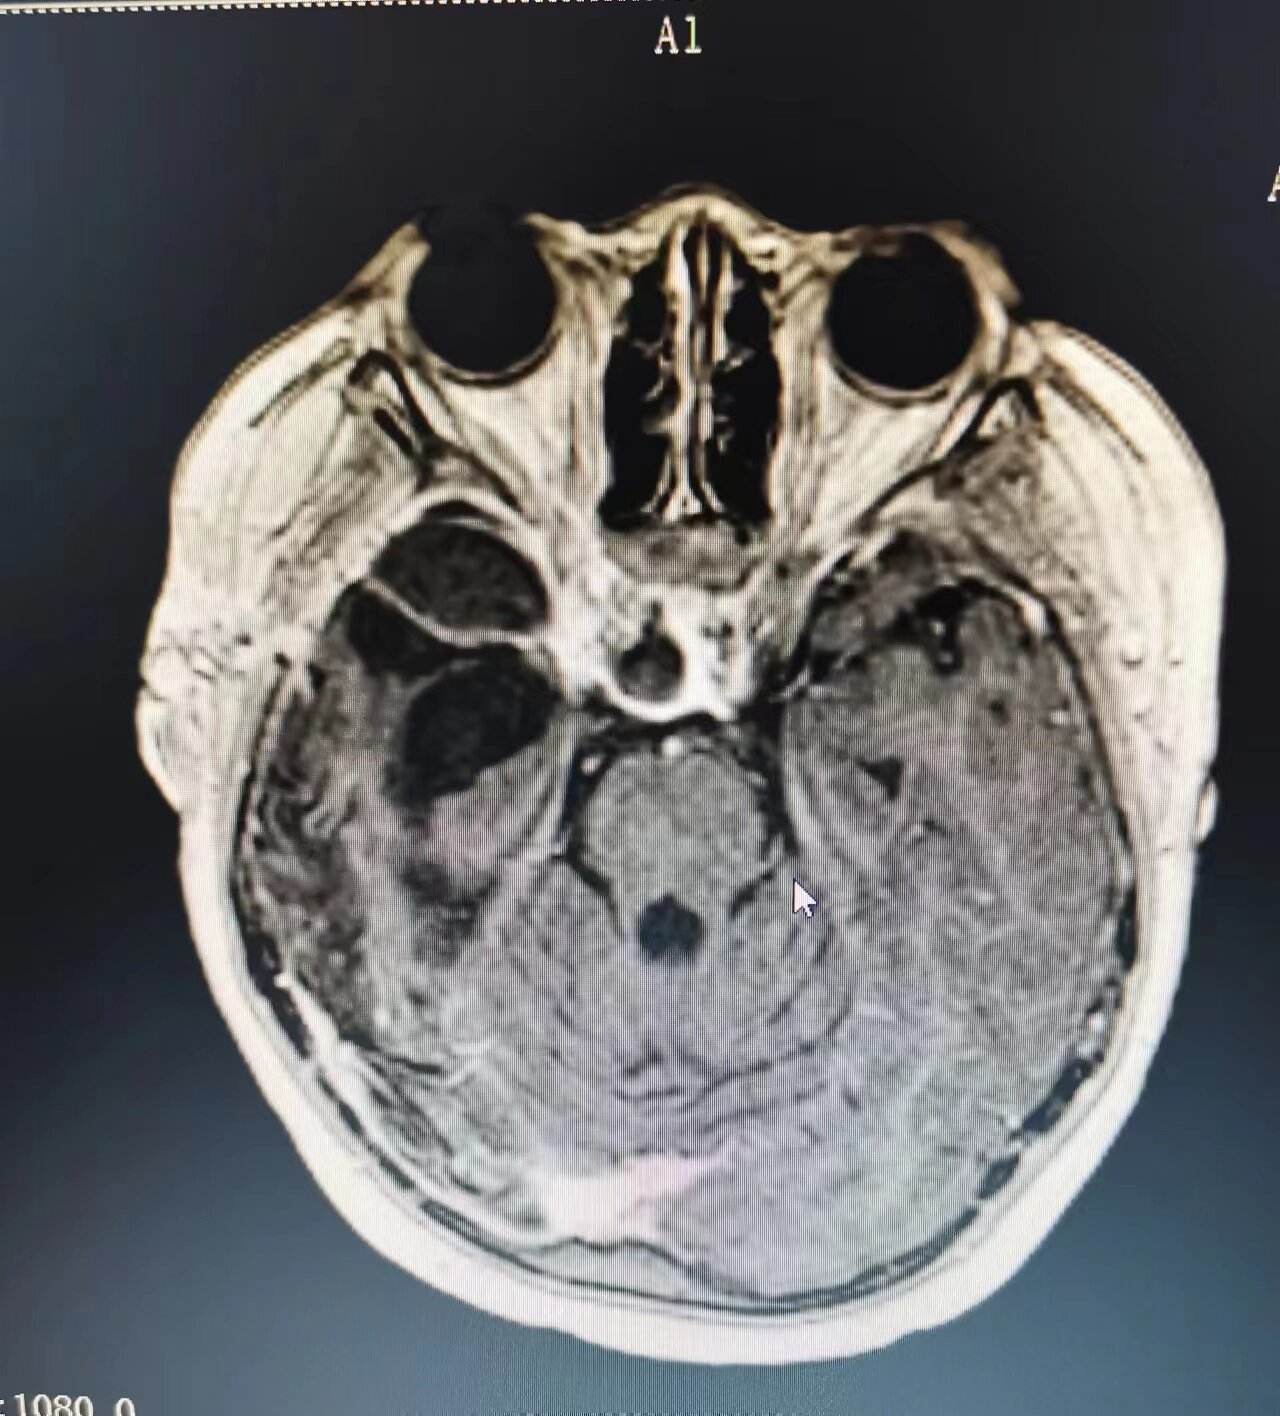

市二院放療科主任趙亮接診后,帶領(lǐng)科室團(tuán)隊(duì)迅速評(píng)估患兒病情,發(fā)現(xiàn)強(qiáng)強(qiáng)顱咽管瘤術(shù)后腫瘤殘存,鞍區(qū)占位緊鄰腦干與視神經(jīng)、視交叉分界不清,雙眼失明、左側(cè)肌力下降,發(fā)育遲緩?;純翰∏閺?fù)雜,趙亮主任立即匯報(bào)醫(yī)務(wù)科,由醫(yī)務(wù)科組織全院多學(xué)科會(huì)診(MDT),邀請影像科、神經(jīng)內(nèi)科、神經(jīng)外科、小兒內(nèi)分泌科、腫瘤內(nèi)科等相關(guān)科室專家會(huì)診討論,參考診療規(guī)范及國內(nèi)外文獻(xiàn),結(jié)合放療科三維放療技術(shù)優(yōu)勢,考慮到患兒年齡小,三維適型調(diào)強(qiáng)放療對接近關(guān)鍵結(jié)構(gòu)的不規(guī)則形狀腫瘤具有高度靶向一致性,同時(shí)能最大限度減少對周圍正常組織輻射照射等技術(shù)優(yōu)勢,趙亮主任與患兒及家屬充分溝通,制定了以三維適型調(diào)強(qiáng)放射治療為主的綜合治療方案。

隨后,患兒開始進(jìn)行三維放療,經(jīng)過13次治療后,患兒每日晨起出現(xiàn)短暫復(fù)明,雙眼光感較前好轉(zhuǎn)。放療結(jié)束,患兒病情較之前明顯好轉(zhuǎn),目前患兒病情得到有效控制,整個(gè)治療過程患者無任何不適。